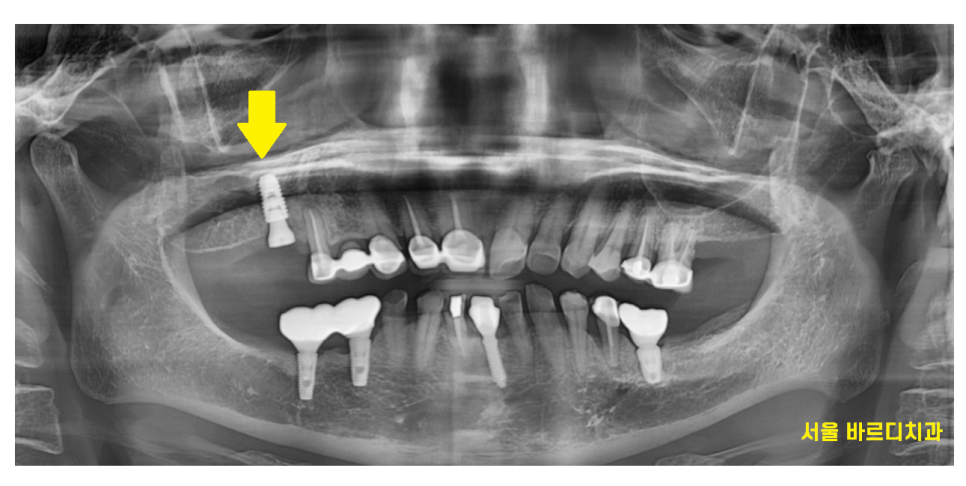

23.07.31

암사동 치과에서 임플란트 치료 진행하였습니다.

3년동안의 골다공증 치료

뼈가 약하신 환자분이셔서

뼈이식까지 진행 후 수술을 했는데요.

돔 형태로 예쁘게 상악동이 올라갔네요~

수술이 아주 잘되었습니다.